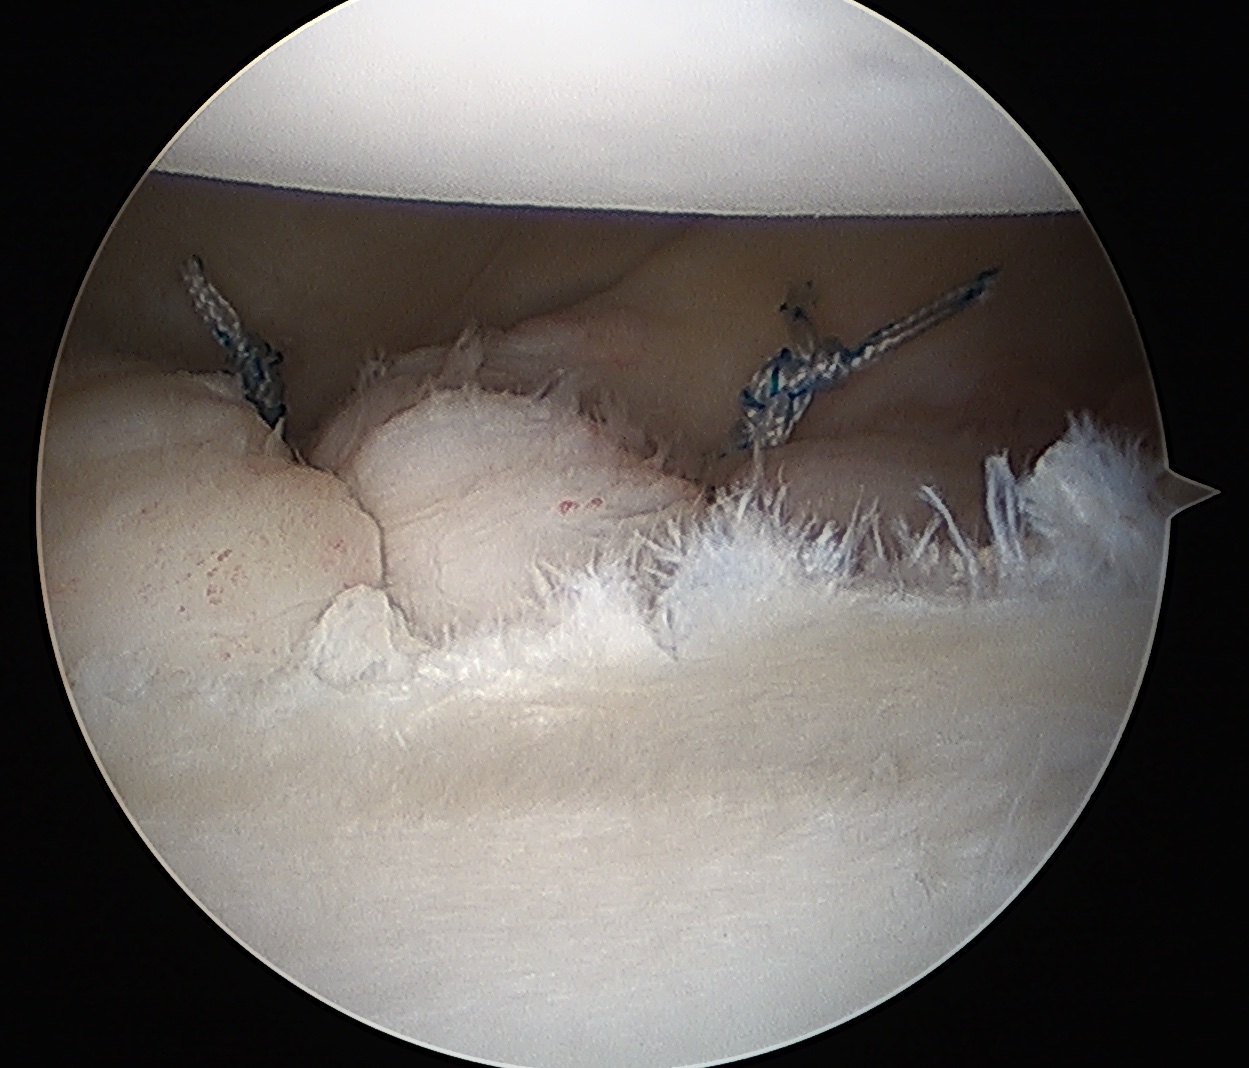

Insert anchors

Inferior anchor at 5.30 o'clock

- curved anchor guide / trans-subscapularis

- on rim of glenoid

Other anchors typically at 3 and 4 o'clock

Pass sutures and tie knots

Typically curved suture passers

Aim to tighten capsule medially and superiorly onto glenoid